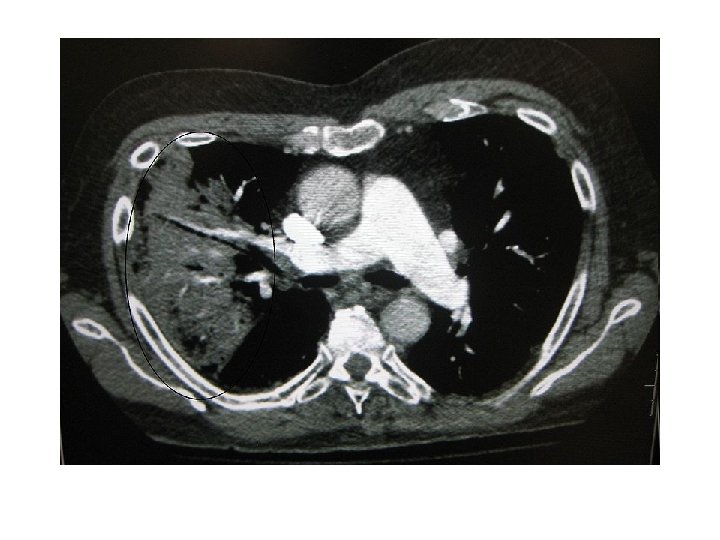

A chest X-ray showing a very prominent wedge shaped pneumonia in the right lung